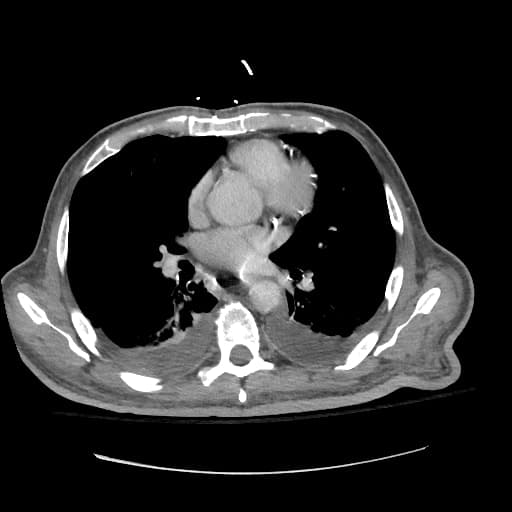

Siêu âm nội soi

Hình ảnh siêu âm nội soi hướng tâm của ung thư thực quản. Khối u thực quản đoạn dưới dạng giảm âm, không đều, xâm lấn vào lớp áo ngoài (adventitia/subserosa): ung thư T3.

Các hạch bạch huyết cạnh thực quản được phát hiện (hình thứ ba), kích thước tối đa 1 cm: ung thư N1.